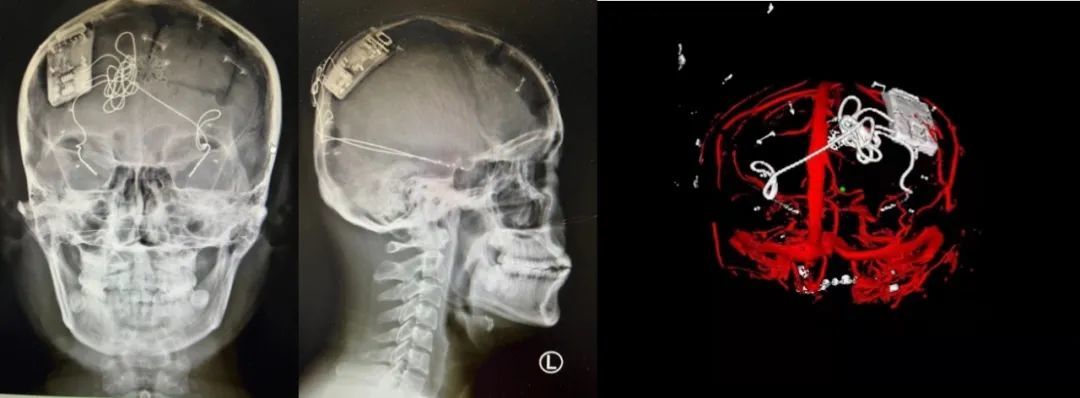

神外前沿訊,2022 年 3 月 9 日,首都醫(yī)科大學(xué)宣武醫(yī)院院長(zhǎng)趙國(guó)光教授,神經(jīng)外科單永治教授帶領(lǐng)的神經(jīng)外科立體定向與功能性腦疾病組團(tuán)隊(duì),成功為一名難治性癲癇患者(雙側(cè)顳葉癲癇)施行了閉環(huán)反應(yīng)性神經(jīng)刺激系統(tǒng) Epilcure?注冊(cè)臨床試驗(yàn)植入手術(shù)(參考閱讀:快訊 | 全國(guó)首款癲癇閉環(huán)刺激系統(tǒng)的注冊(cè)臨床試驗(yàn)啟動(dòng))。

這標(biāo)志著由宣武醫(yī)院作為牽頭單位的 Epilcure?國(guó)家藥品監(jiān)督管理局(NMPA)注冊(cè)臨床試驗(yàn)的首例入組首戰(zhàn)告捷;也標(biāo)志著經(jīng)過(guò)國(guó)內(nèi)臨床與基礎(chǔ)研究團(tuán)隊(duì)艱苦卓絕的努力與攻關(guān),具備自主知識(shí)產(chǎn)權(quán)的“腦機(jī)接口”高新技術(shù)產(chǎn)品,走到了全方位臨床使用前的最后一步。

據(jù)了解,閉環(huán)反應(yīng)性神經(jīng)刺激系統(tǒng)為“腦機(jī)接口”在臨床領(lǐng)域的重要應(yīng)用,該技術(shù)通過(guò)將人工智能芯片植入顱骨,顱內(nèi)電極植入腦內(nèi),晝夜無(wú)間斷監(jiān)測(cè)腦電節(jié)律,一旦預(yù)測(cè)到即將發(fā)生的癲癇,即啟動(dòng)外源性干擾節(jié)律,直接阻斷致癇灶內(nèi)的癲癇形成,精準(zhǔn)的控制環(huán)路的活動(dòng)。

本次手術(shù)過(guò)程順利,術(shù)中刺激器各項(xiàng)指標(biāo)均工作正常,術(shù)后重建顯示電極位置精準(zhǔn),腦電信號(hào)清晰?;颊邽槟行?,入院后診斷為雙側(cè)顳葉癲癇,此類(lèi)癲癇為開(kāi)顱手術(shù)的相對(duì)禁忌癥,在藥物無(wú)法控制的情況下,傳統(tǒng)治療效果欠佳 。

術(shù)前經(jīng)過(guò)宣武醫(yī)院癲癇多學(xué)科專(zhuān)家團(tuán)隊(duì)詳細(xì)的臨床評(píng)估,包括視頻腦電監(jiān)測(cè)、頭顱磁共振及三維 CT 掃描、腦核醫(yī)學(xué)檢查等,全面評(píng)估了患者病情及致癇灶定位情況。

由于患者臨床診斷為雙側(cè)顳葉癲癇伴海馬硬化,無(wú)法通過(guò)致癇灶切除等傳統(tǒng)外科手術(shù)方式獲益,決定進(jìn)行閉環(huán)反應(yīng)性神經(jīng)刺激系統(tǒng)植入手術(shù)治療。并根據(jù)閉環(huán)神經(jīng)刺激技術(shù)特點(diǎn),為患者“量身定制”植入方案,尤其是電極植入位點(diǎn)和脈沖發(fā)生器固定部位等,為手術(shù)的順利實(shí)施奠定了良好基礎(chǔ)。

團(tuán)隊(duì)根據(jù)術(shù)前計(jì)劃,在手術(shù)機(jī)器人輔助下完成雙海馬長(zhǎng)軸電極及 IPG 植入,術(shù)后重建顯示電極位置精準(zhǔn),腦電信號(hào)清晰。術(shù)后第二天,患者即下床活動(dòng),身體狀況恢復(fù)良好。